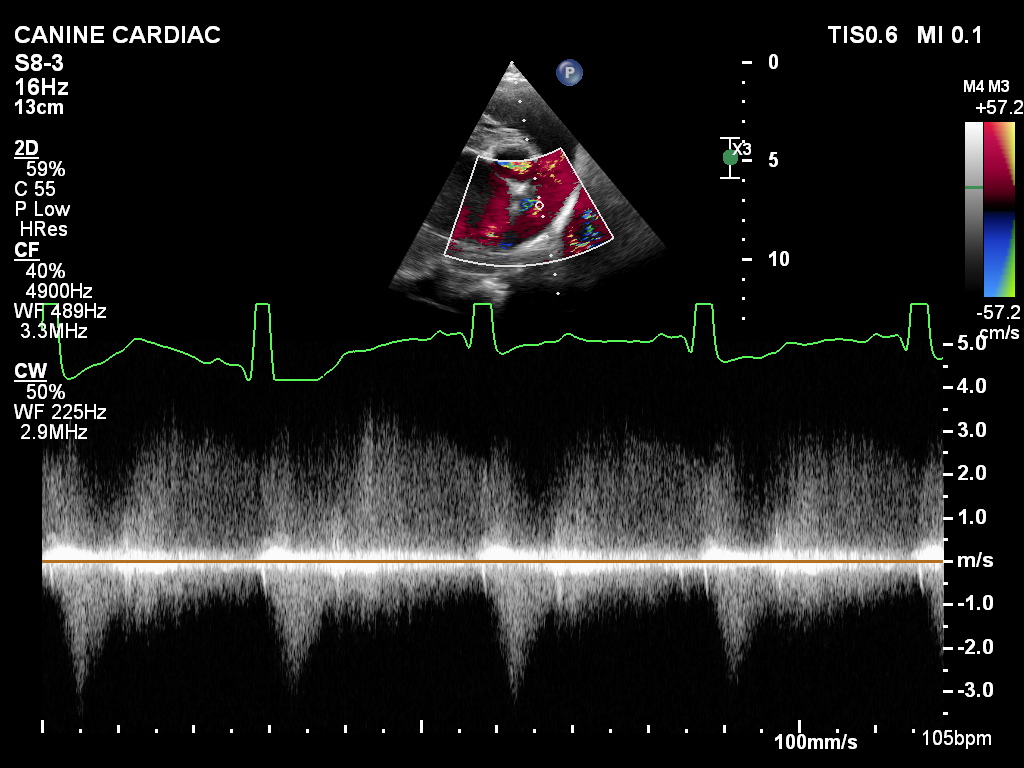

An echocardiogram showed a massive left side with both the Atrium and ventricle enlarged. The left atrium was so enlarged it made it difficult to get our normal views, but we found a clear PDA with a continuous flow in the pulmonary artery and a ductus of approximately 1.2cm. [See pics]